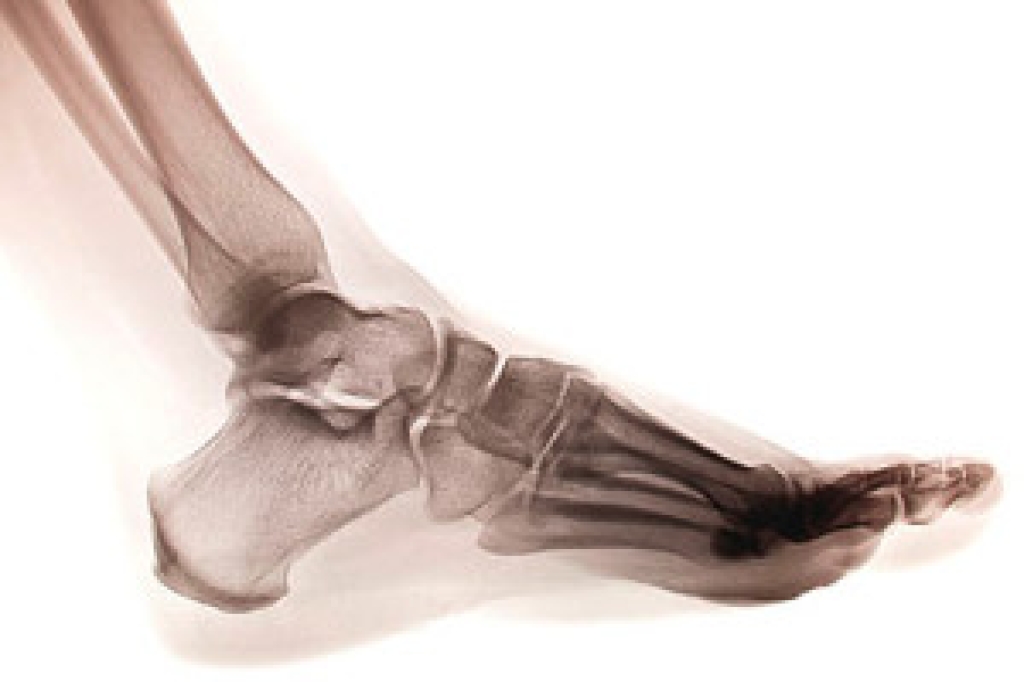

There are several bones in each foot, and a stress fracture occurs when there is a hairline break in one of the small bones. It often happens as a result of repetitive stress the feet endure from running or from frequently participating in jumping activities. The fractures are typically very small, despite how painful they can be. Many people choose to ignore the nagging pain in their foot, and it often becomes worse if it is not promptly treated. It may be a common injury among runners who increase their speed and frequency of running too soon, and this could gradually cause a stress fracture. This can be a result of a lack of strength and endurance from the muscles that cannot cope with added support that is needed when that activity increases. Additional reasons why stress fractures may occur include having an abnormal foot structure, wearing shoes that do not fit correctly, or having previous stress fractures. If you think you have endured this type of fracture, please speak with a podiatrist as quickly as possible who can properly treat this condition.

Stress fractures occur in the foot and ankle when muscles in these areas weaken from too much or too little use. The feet and ankles then lose support when walking or running from the impact of the ground. Since there is no protection, the bones receive the full impact of each step. Stress on the feet can cause cracks to form in the bones, thus creating stress fractures.

Pain from the fractures occur in the area of the fractures and can be constant or intermittent. It will often cause sharp or dull pain with swelling and tenderness. Engaging in any kind of activity which involves high impact will aggravate pain.